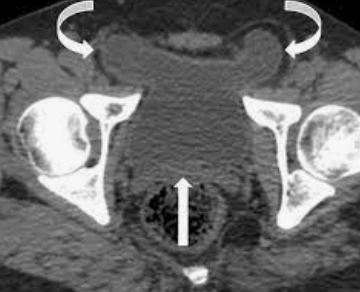

6

Q

A

Bladder ears (“transitory exztraperitoneal herniation of the bladder” into the inguinal canal

Note: This is a transient finding during Valsalva and often associated with inguinal hernias.